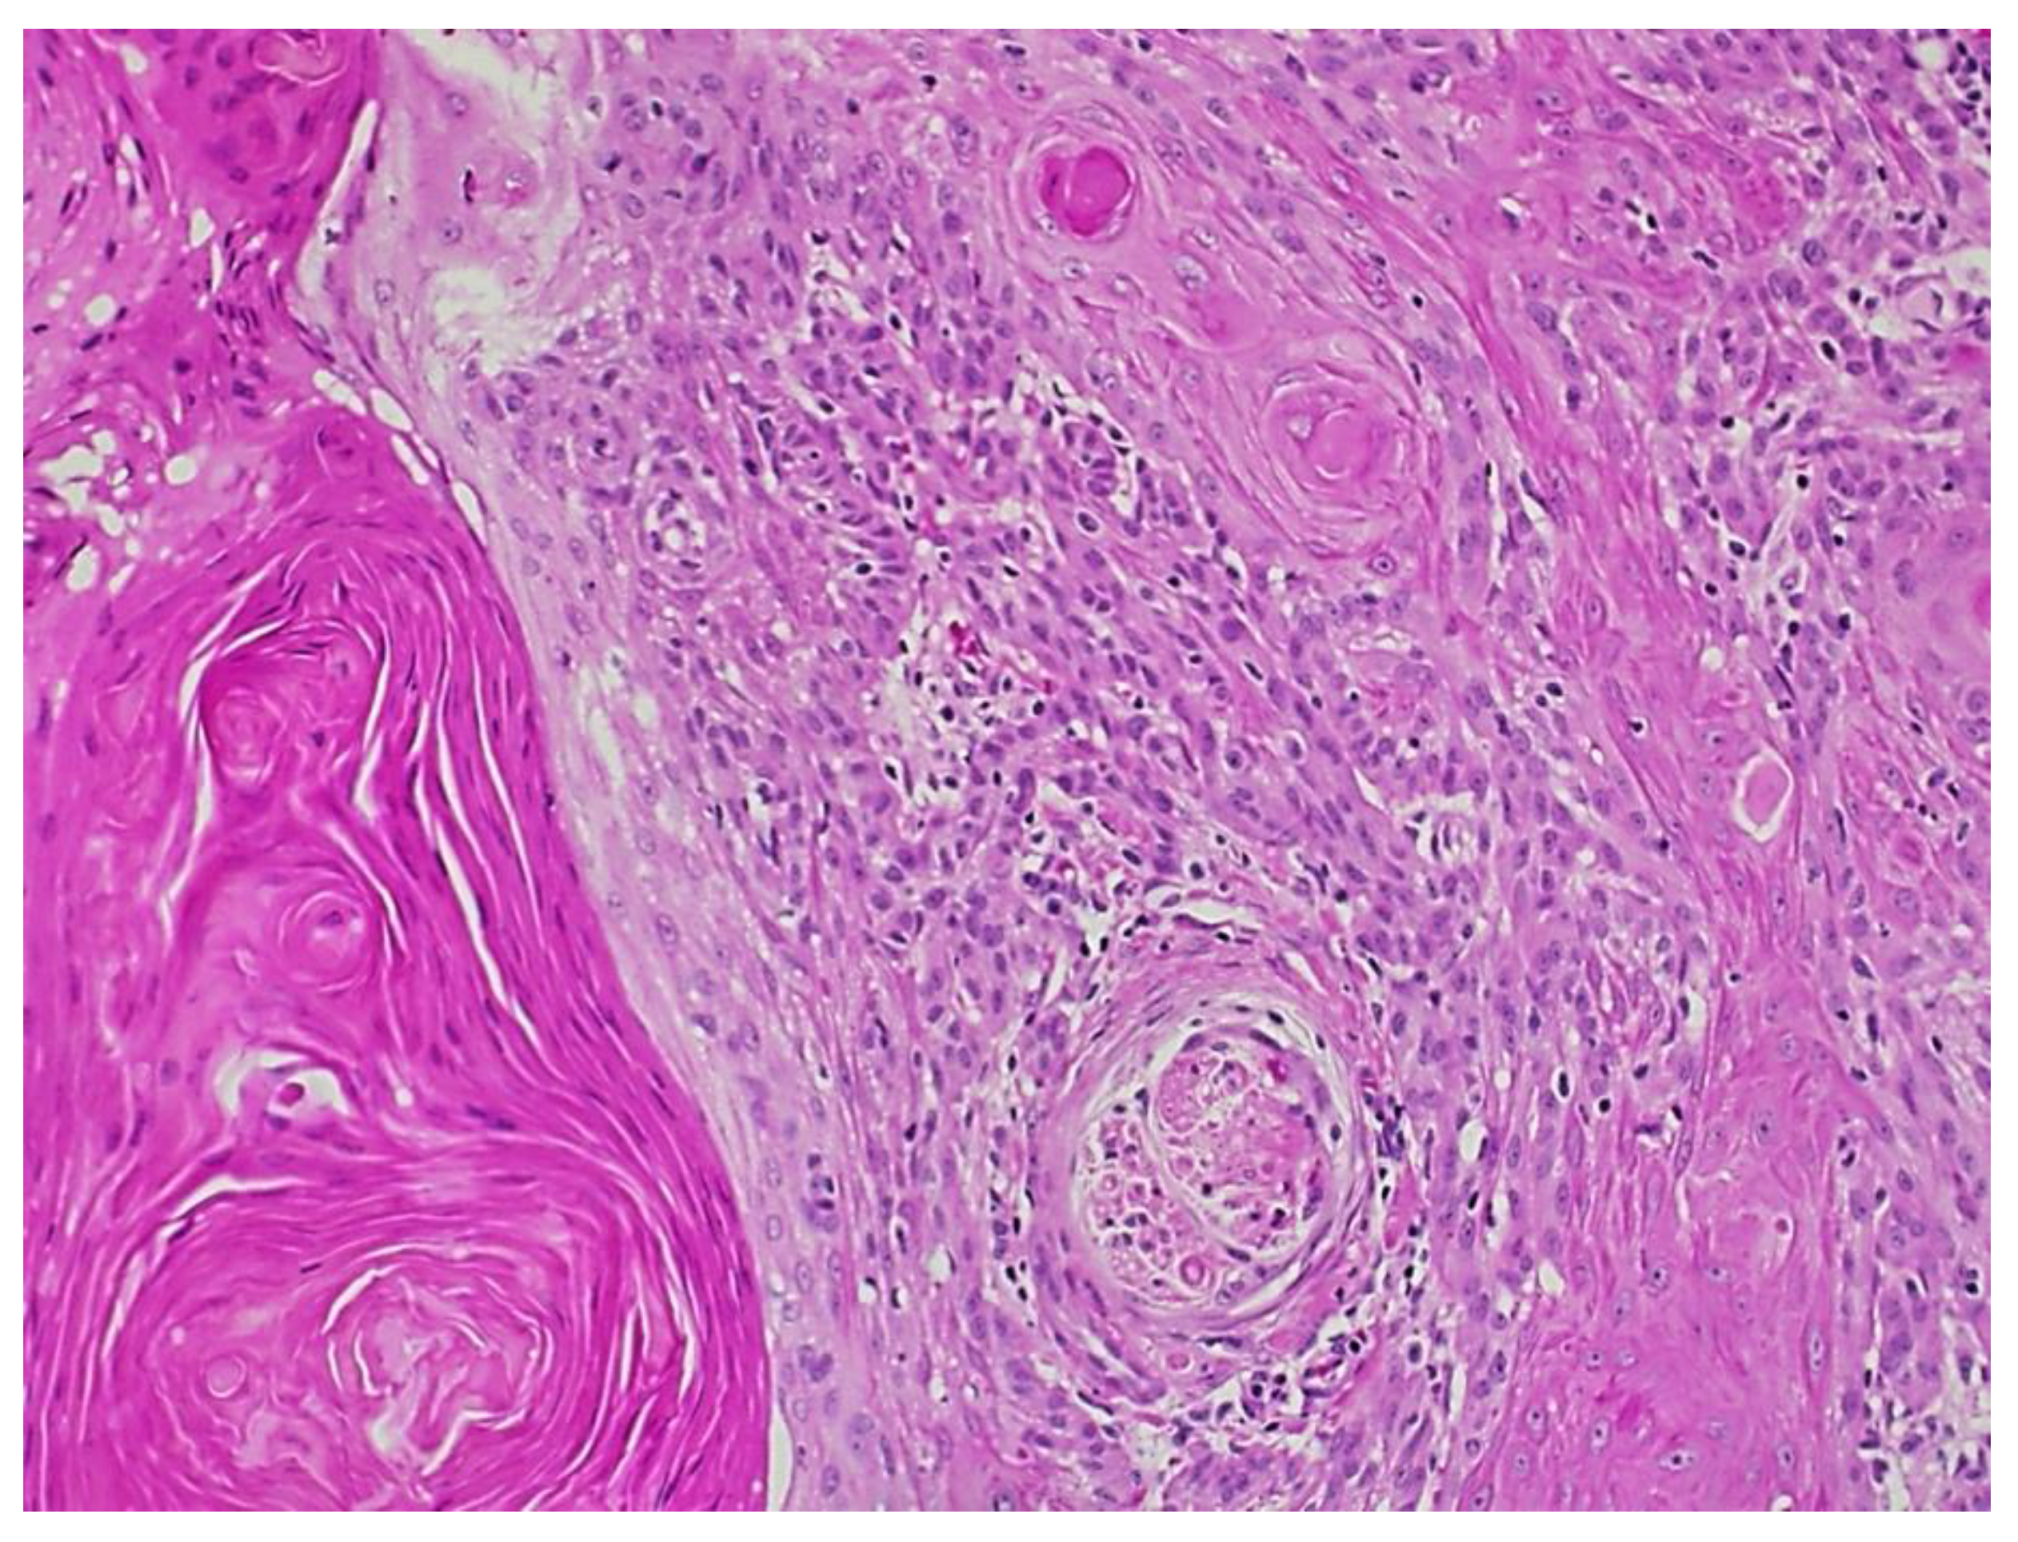

Figure 3.

Squamous cell carcinoma with acantholytic features.